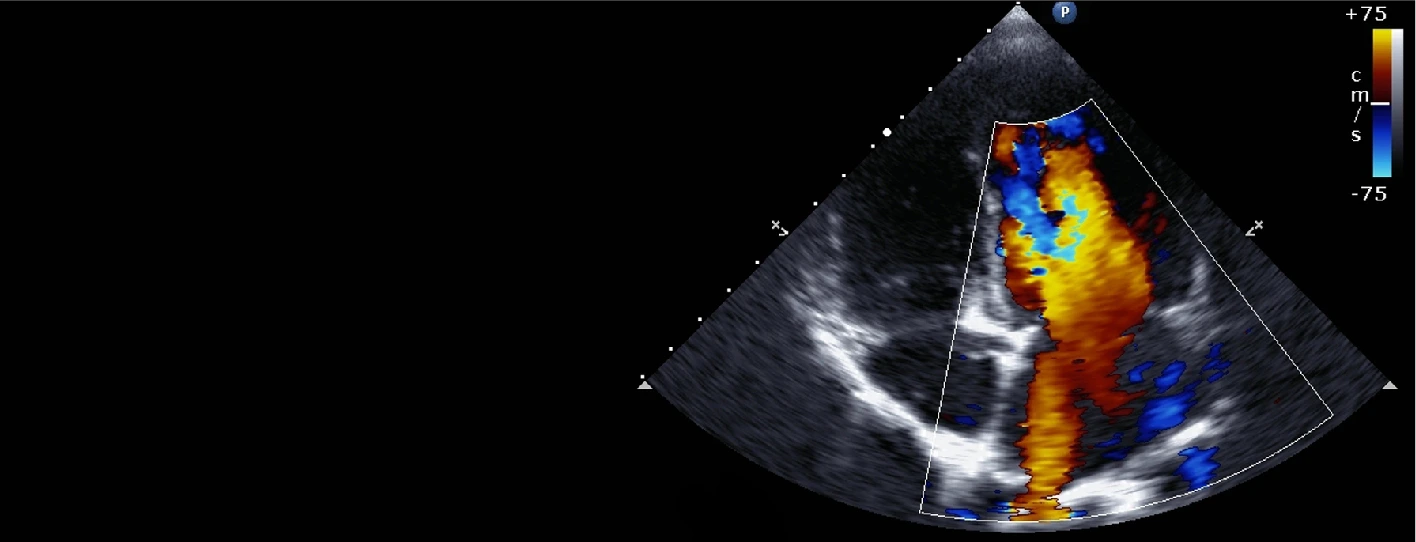

A color Doppler test is a non-invasive imaging technique that uses sound waves to visualize blood flow in your blood vessels.

Unlike traditional ultrasound, which only shows the structure of the vessel, color Doppler adds color to the image to indicate the direction and speed of blood flow. This helps doctors identify abnormalities such as blockages, clots, or narrowing of blood vessels